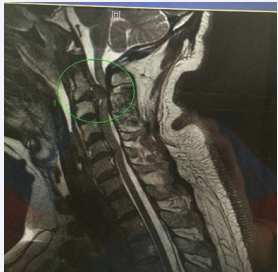

at C2/3 severely compressing the spinal cord (Figure 2),

Figure 2: A sagital T2 image of the cervical spine demonstrating near complete occlusion of the spinal canal by C2/3 disc hernination with associated myelomalecia of the spinal cord.